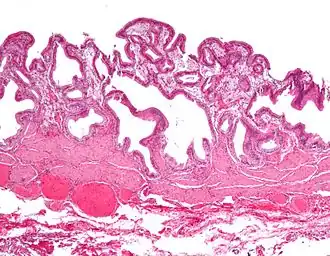

| Micrografia da colesterolose da vesícula biliar. Mancha de H&E. | |

Micrografia da colesterolose da vesícula biliar.

Micrografia da colesterolose da vesícula biliar. -